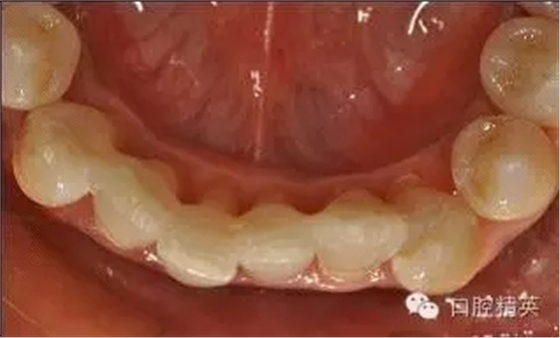

本病例 :女 34歲,主訴刷牙出血,覺(jué)牙齒輕度松動(dòng)一年。

檢查見(jiàn)大量齦上及齦下結(jié)石,探診出血,牙周袋較深,32-42 II度松動(dòng)。X線片顯示牙槽骨水平吸收。

診斷:成人慢性廣泛性中度牙周炎。

治療計(jì)劃:口腔衛(wèi)生宣教,刷牙指導(dǎo),齦上潔治,齦下刮治術(shù),下頜牙33-43牙周固定。

治療前: